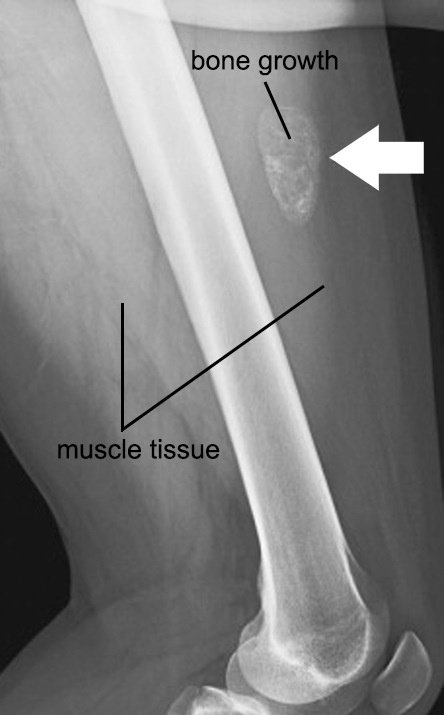

Myositis osiffication

ودى اسوأهم

اخر حاجه اننا ممكن نشوف نفس الفكرة مع muscle contusion برضه بتبقى إصابة بيحصل معاها مضاعفات واتكلمنا عنها قبل كده

وممكن مع الوقت لو أهملت تبقى

chronic and old complications

وع حسب شدة الكدمة

شفنا أكثر من شخص كان

old muscle contusion .